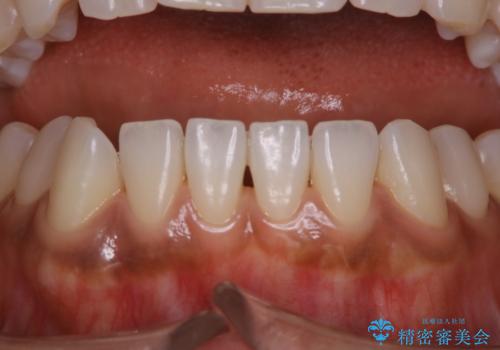

全体的な治療の開始前に着色取り